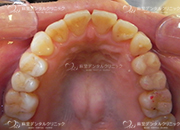

セラミックインレー

当院で扱っているセラミックインレーにはe.max(イーマックス)とジルコニアがあります。

ジルコニアインレーの方が強度がありますが、e.maxインレーの方が色が合わせやすく自然な仕上がりになる事が多いです。

ジルコニアインレーはCAD/CAMという技術により製作された物を使用し、e.max(イーマックス)はプレスいう技法で製作された物を扱っています。